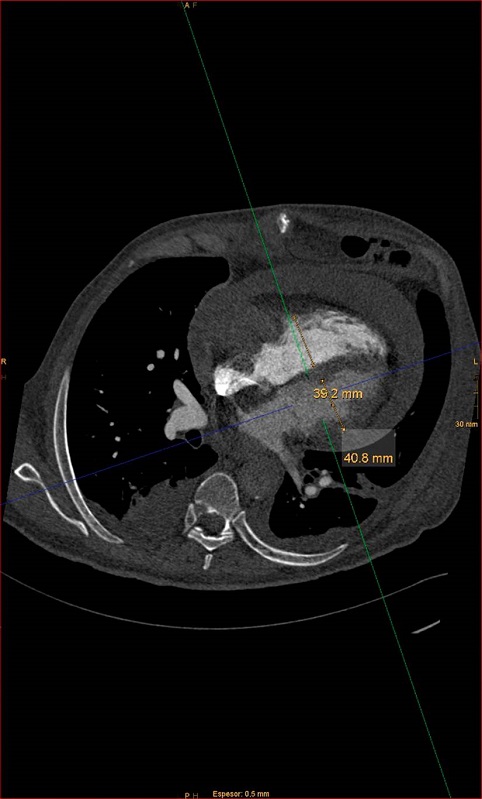

En la analítica, destaca un dímero D de 2322 ng/mL (normalidad: 0-500). Se realiza una angiografía por tomografía computarizada (angio-TC) de arterias pulmonares que descarta TEP, pero en la que se observa un marcado derrame pericárdico y una masa cardíaca de 70x35 mm en la aurícula derecha, que se confirma con un ecocardiograma. El paciente ingresa en la planta de cardiología y se continúa el estudio con una resonancia magnética (RM) en la que se aprecia que la masa infiltra la pared libre de la aurícula derecha con invasión del pericardio visceral (figura 3). Durante la realización de dicha prueba el paciente presenta deterioro clínico con hipotensión, por lo que, ante la sospecha de taponamiento cardíaco, ingresa en la unidad coronaria, donde se le realiza una pericardiocentesis urgente, obteniéndose 1 litro de líquido hemorrágico con anatomía patológica negativa para células tumorales. Más tarde se completa el estudio con una tomografía computarizada (TC) toraco-abdomino-pélvica en la que se observa una lesión expansiva (LE) sólida, hipocaptante en el segmento 6 del hígado, sugestiva de metástasis, que en la tomografía por emisión de positrones (PET)-TC no presenta significado patológico y se repite la RM cardíaca que muestra una masa sugestiva de angiosarcoma. Se realiza una punción con aspiración de aguja fina (PAAF) de la LE hepática que, con técnicas de inmunocitoquímica, resulta positiva para los marcadores CD34 y CD31, compatible con angiosarcoma.

El ECG puede ser normal, aunque también pueden aparecer cambios inespecíficos del segmento ST y bajos voltajes. En la radiografía de tórax se observa cardiomegalia. Para su diagnóstico inicial se recurre normalmente a la ecocardiografía. Posteriormente, se puede ampliar el estudio con RM, TC o PET. Pero la caracterización definitiva del tumor requiere obtener muestras para su estudio anatomopatológico5.